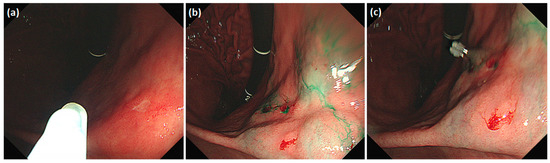

Detailed endoscopic clipping procedures have been described previously [12,13], and ICG injection and hemoclip application were performed at the same time on the day before surgery. As previously reported [14,19,24,25], we endoscopically injected ICG (Dongindang Pharmaceutical Co., Siheung-si, Korea) solution into the gastric submucosal layer at four quadrants around the tumor, on the day before performing NIR fluorescence-guided surgery. Each of the four quadrants was injected with 0.6 mL of 0.625 mg/mL ICG solution for a total of 1.5 mg of ICG. In addition, endoscopic hemoclips were used to grossly delineate the tumor. Two hemoclips were placed proximal to the tumor (Figure 1).

Figure 1.

Preoperative tumor localization: (a) endoscopic identification of the tumor; (b) submucosal ICG injection around the tumor in each quadrant; (c) additional application of hemoclips proximal to the tumor.